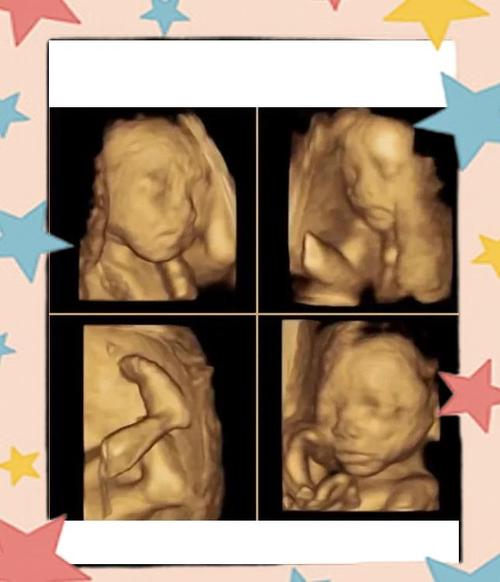

(图片来源网络,侵删)- 测量双顶径、头围、腹围、股骨长等指标,评估胎儿大小是否符合孕周。